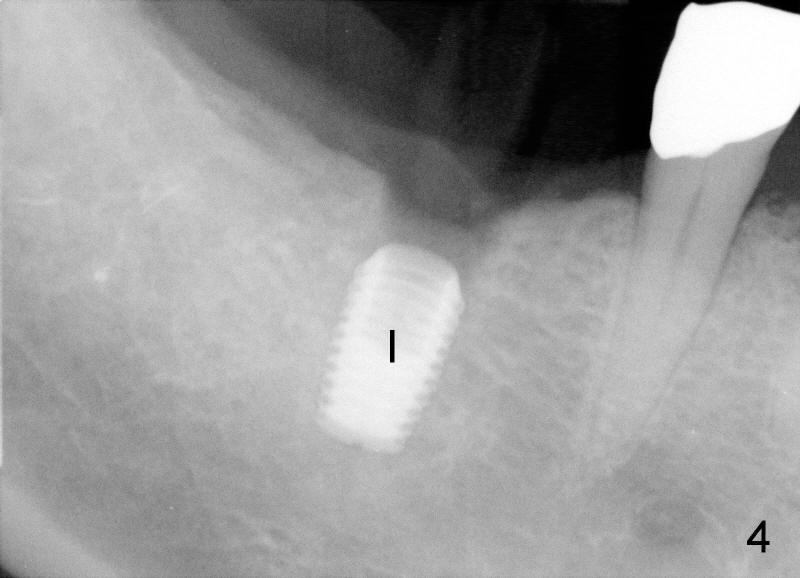

Fig.6: there is bone resorption around the implant (I) 3 months postop ( >, as compared to Fig.4 immediately after placement). After debridement, bone resorption is reduced to the distal crest of the implant (Fig.10 >), return to main article Xin Wei, DDS, PhD, MS 1st edition 11/10/2011, last revision 04/06/2012 |